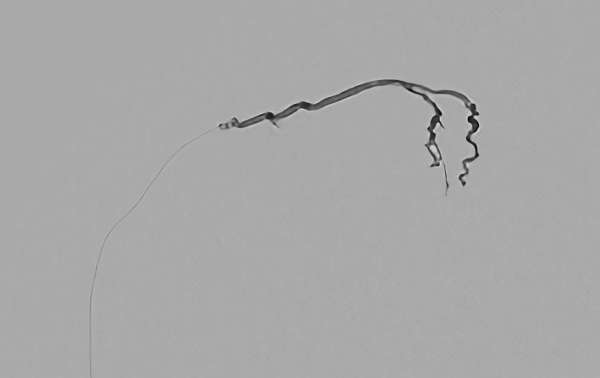

No.622 手術中